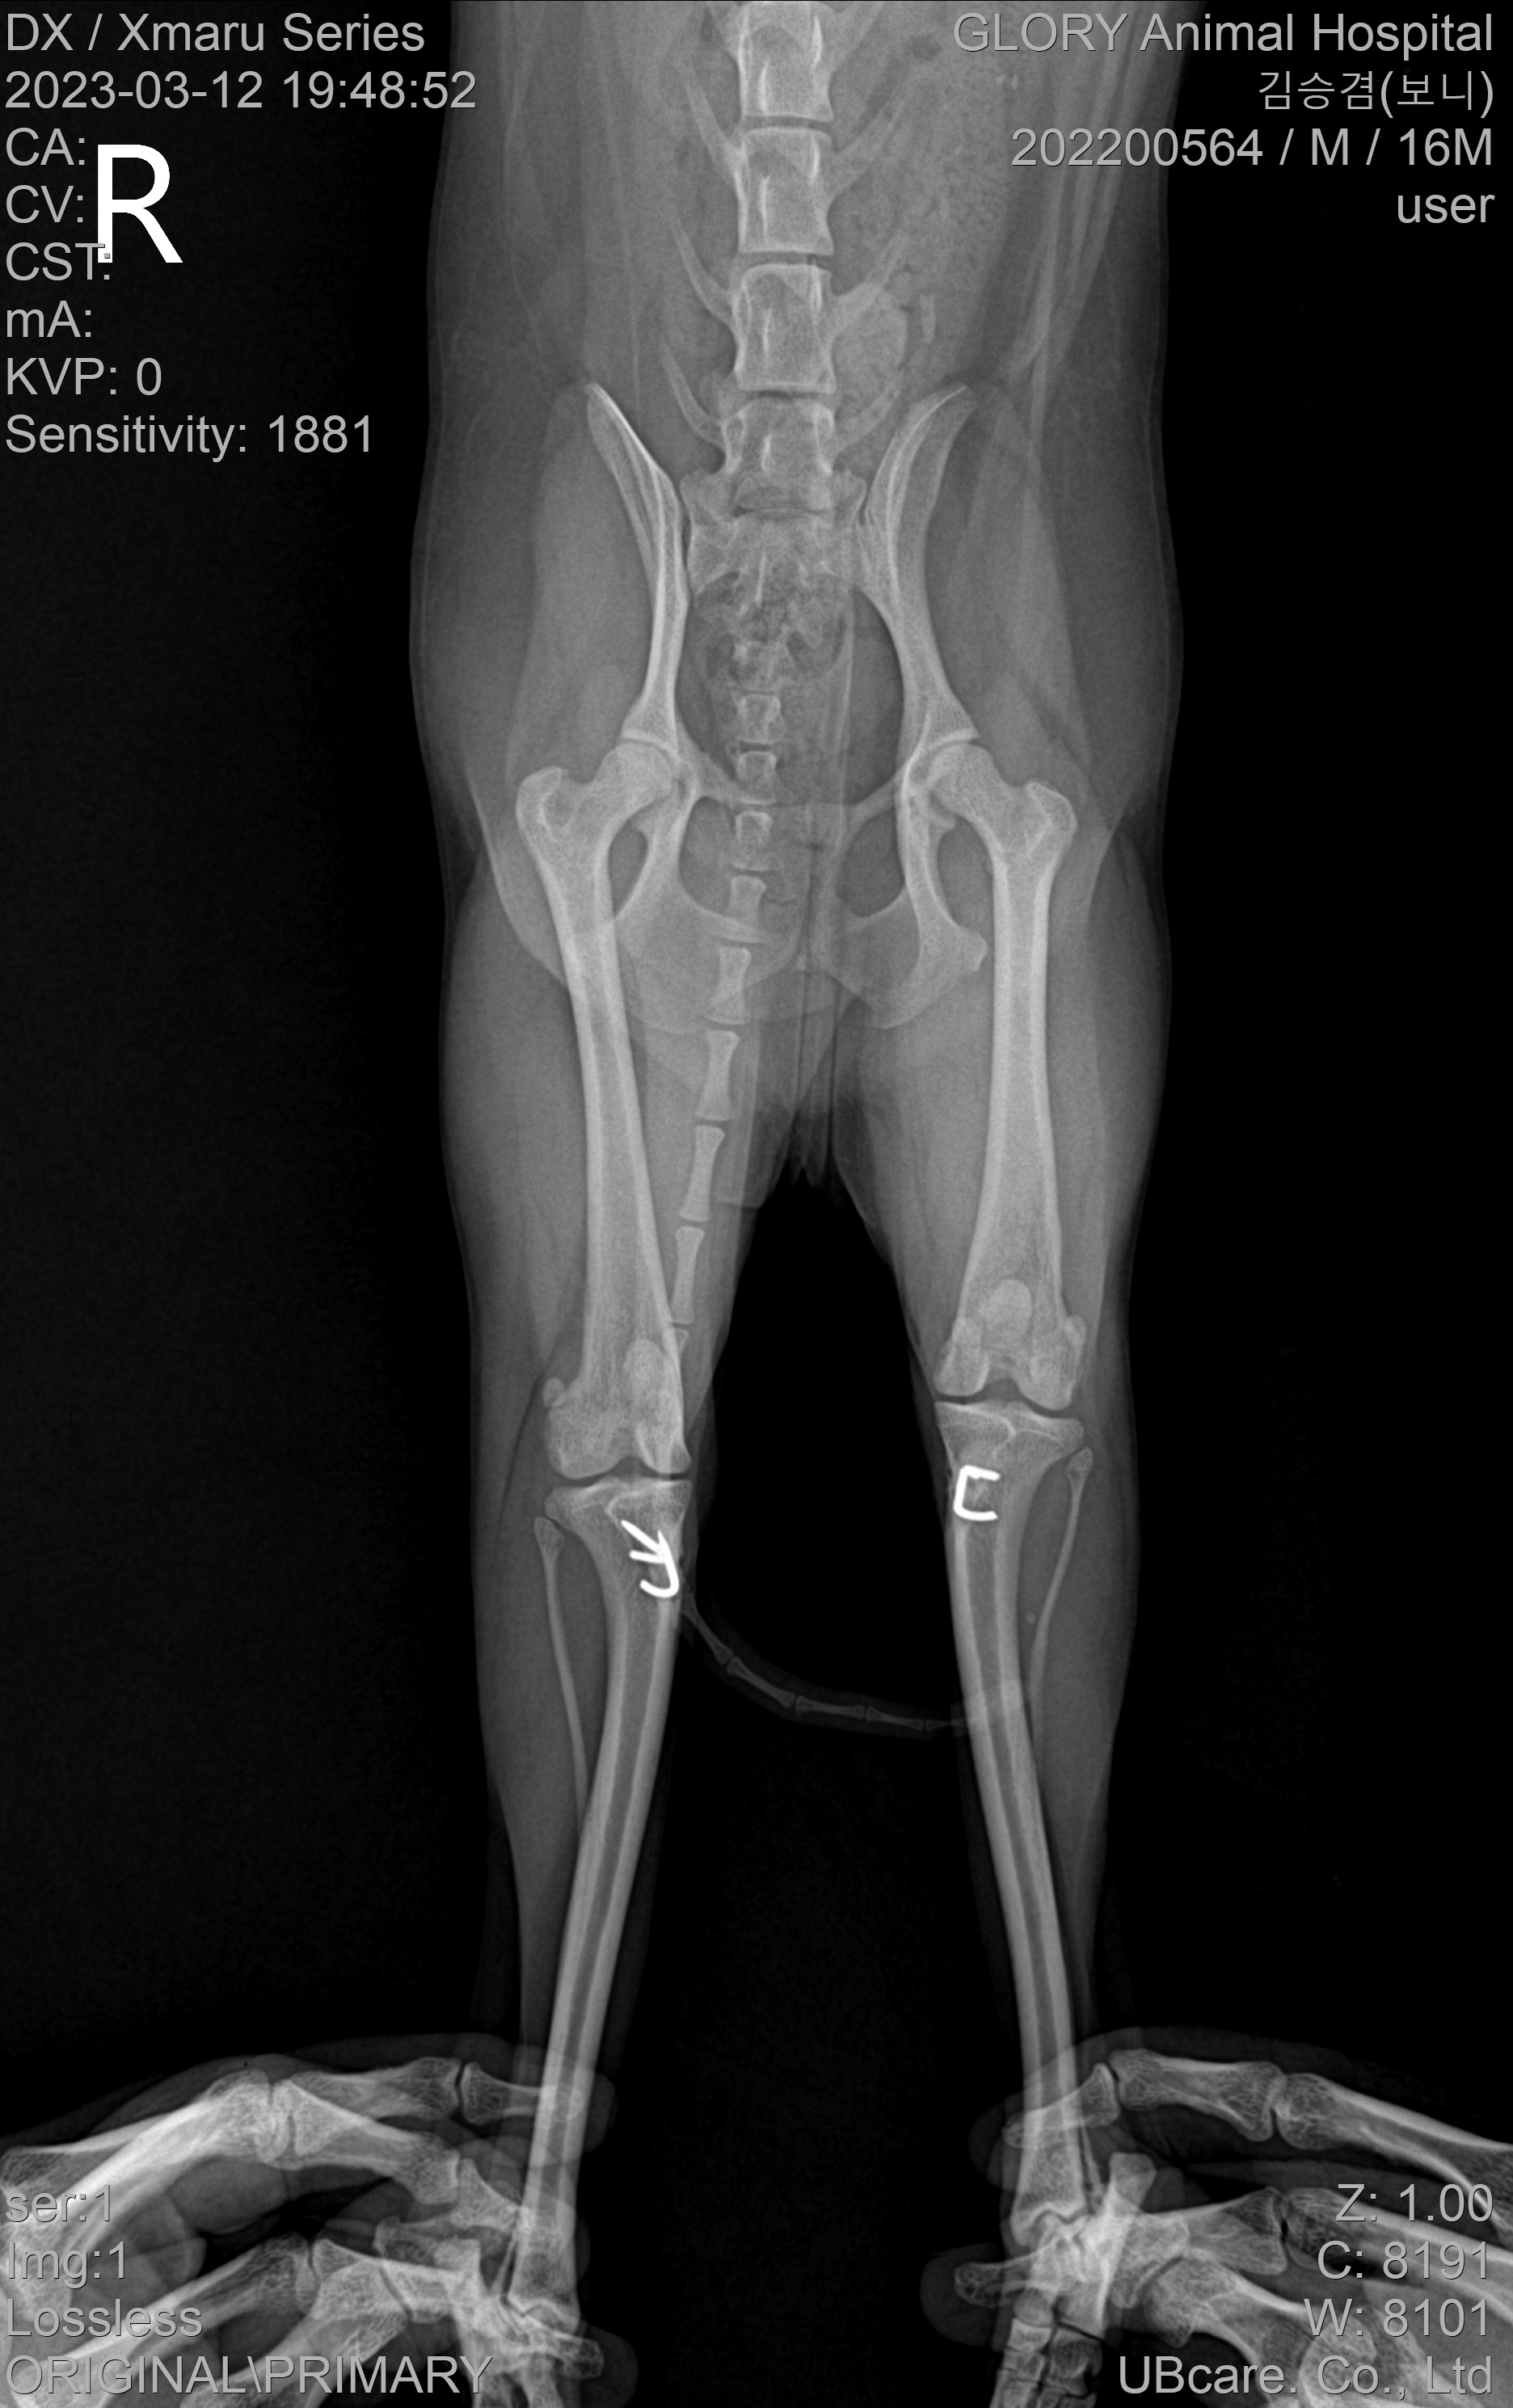

드디어 실을 푸는 날입니다~! 실밥을 풀고 중간점검을 하는 날인데 X-ray 결과 슬개골은 정상위치에 있고 주변 조직에는 문제가 없다고!!